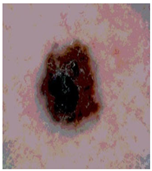

![]() | ![]() | ![]() | ![]() |

| Img1 | --- Pixel Intensity (0–255) ---> | ||

| Original Image | Th2 | Th3 | Th4 | Th5 |

|---|---|---|---|---|

![]() Img1 | ![]() | ![]() | ![]() | ![]() |